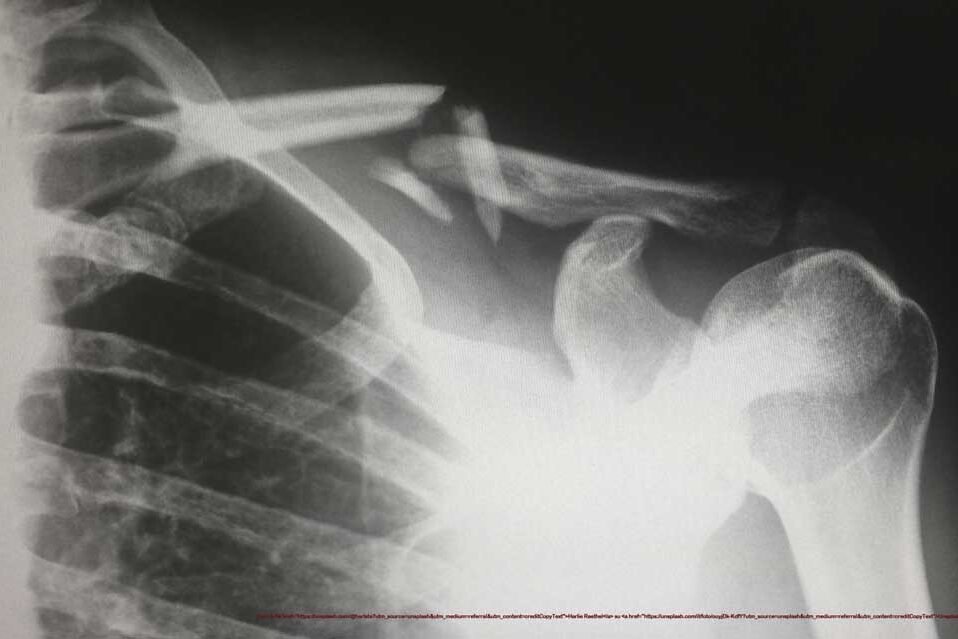

Lussazione della clavicola di alto grado. Questo è un tipo di infortunio abbastanza raro però succede molto frequentemente quando i giocatori di calcio battono spalla a spalla, oppure atterrano sulla spalla.

Nella spalla c’è una piccola articolazione che si chiama acromion claveare .

L’acromion è una parte della scapola e la clavicola è chiaramente la clavicola, quell’osso tubolare che abbiamo sul davanti – ne abbiamo 2 uno a sinistra e l’altro a destra – che è un’articolazione statica fatta di ossa che si muovono per millimetri e sono attaccate insieme da piccoli legamenti.

Ma quando abbiamo una lussazione di alto grado significa che tutti i legamenti sono rotti e questa clavicola che è lussata veramente molto in alto non si può più ridurre e non rimane più apposto.